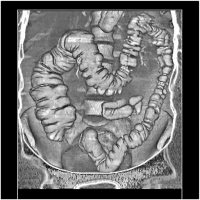

Метод неинвазивного исследования толстого кишечника, основанный на его визуализации с использованием возможностей современной рентгеновской мультиспиральной компьютерной томографии. Это особый вид компьютерной томографии, при которой исследуется толстая кишка. Обычная колоноскопия (не виртуальная) - это эндоскопический метод диагностики, при котором эндоскоп вводится в кишку непосредственно.

Исследования проводятся на компьютерном томографе Toshiba AQUILION 128 срезов с применением газового инсуфлятора Ulrich Medical